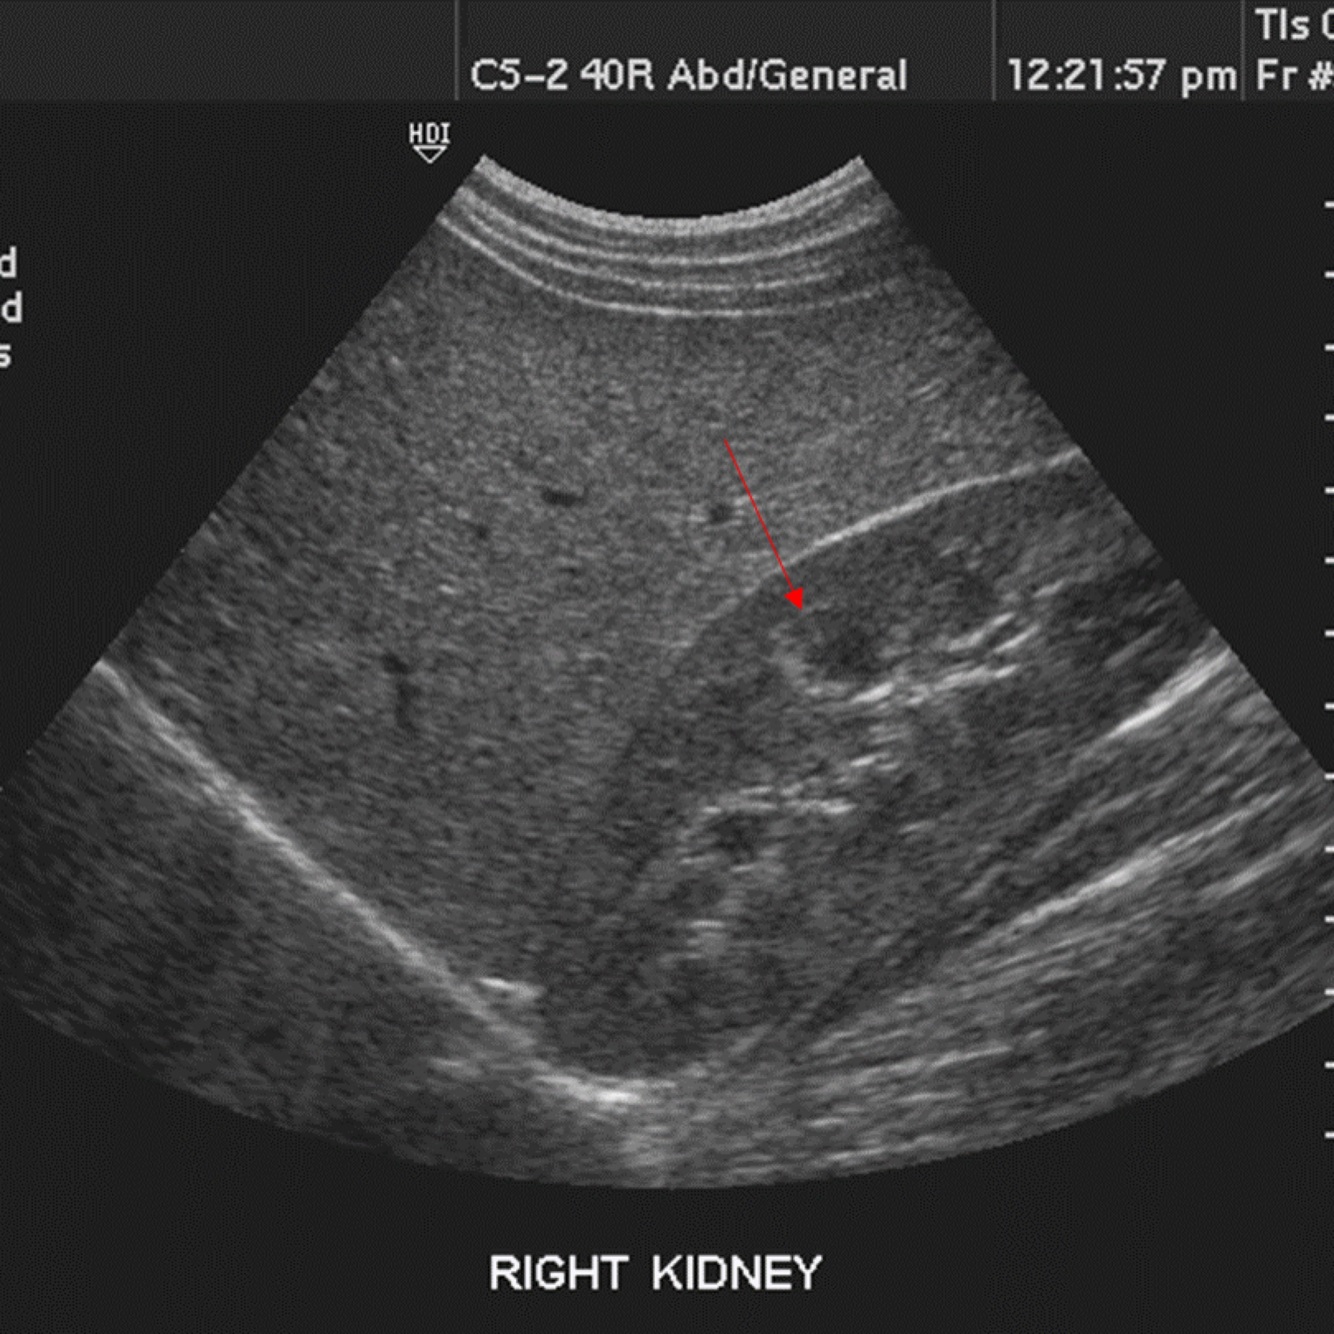

Q

What is the arrow pointing to?

A

The right renal artery